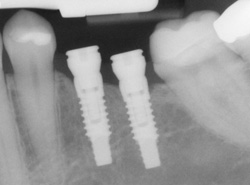

Implants

If you have missing teeth, it is crucial to replace them. Without all your teeth, chewing and eating can destabilize your bite and cause you discomfort. When teeth are missing, your mouth can shift and even cause your face to look older. Implants are a great way to replace your missing teeth, and if properly maintained, can last a lifetime!

An implant is a new tooth made of metal and porcelain that looks just like your natural tooth. It’s composed of two main parts: One part is the titanium implant body that takes the place of the missing root, and the second part is the tooth-colored crown that is cemented on top of the implant. With periodontal treatment, you can smile confidently knowing no one will ever suspect you have a replacement tooth.

In addition to tooth replacement, implants may be used to anchor dentures, especially lower dentures that tend to shift when you talk or chew. For patients with removable partial dentures, implants can replace missing teeth so you have a more natural-looking smile.